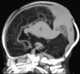

Vein of Galen aneurysm